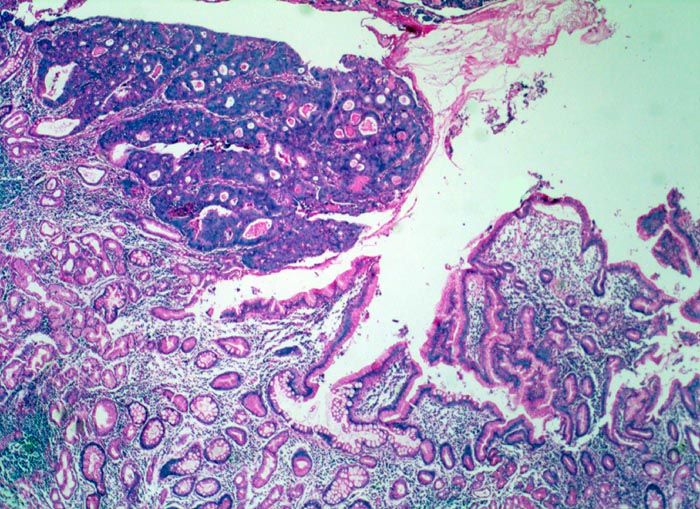

Magenfrühkarzinom

Magenantrum

Die Lamina propria der Antrumschleimhaut ist entzündlich infiltriert. Neben Schleimdrüsen vom Antrumtyp finden sich zahlreiche metaplastische Drüsen mit Becherzellen. Die Mukosa wird von einem polypoiden scharf begrenzten Tumor infiltriert. Aufgrund der vergrösserten Kerne ist das Tumorgewebe deutlich basophiler als die Drüsen der Mukosa. Der Tumor bildet dos à dos liegende Drüsen (kribriformes Wachstumsmuster).

Polypoider Tumor im Magenantrum.

Intramukosal lokalisierte Karzinome des Magens können im Gegensatz zu Adenomen des Kolons in die Lymphknoten metastasieren, obwohl das Karzinom die Lamina muscularis mucosae noch nicht durchbrochen hat.